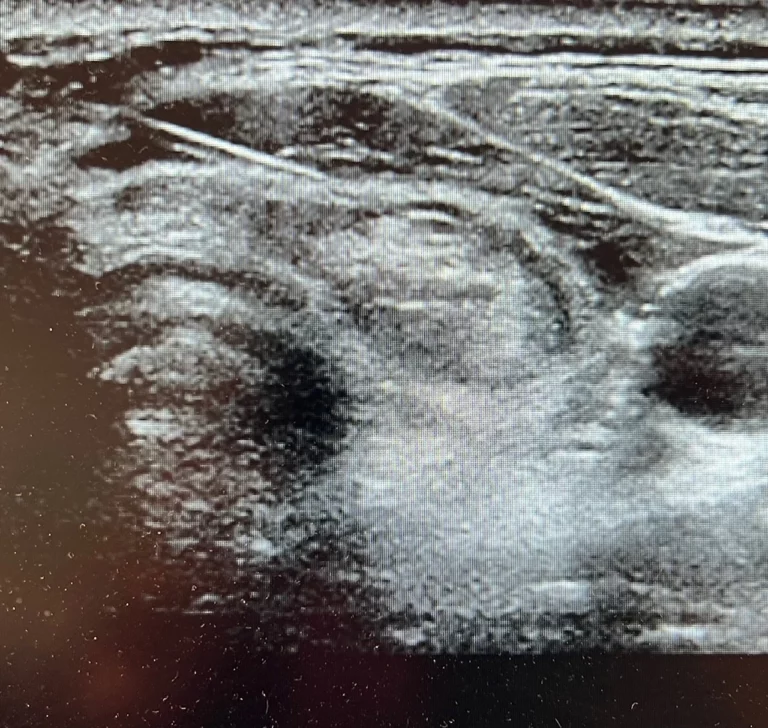

- Chirurgie de la thyroïde et des parathyroïdes.